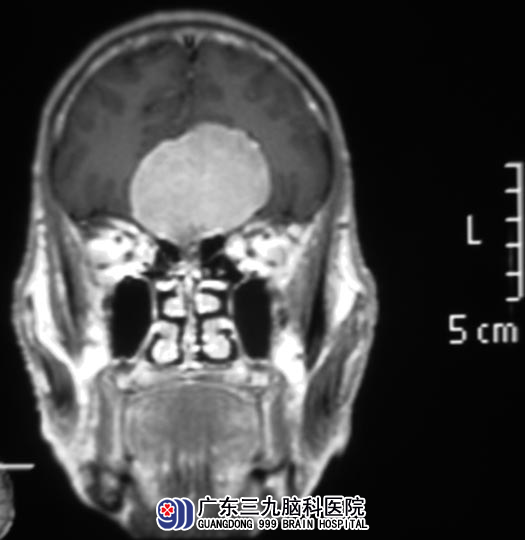

叶老伯,虽然是73岁的老人,但身体一直不错。10天前有头晕,症状较轻,家人都没有引起关注。直到突然出现肢体抽搐,伴神志不清,才慌慌忙忙将老人送当地医院就诊。头颅CT检查提示额部占位,广东三九脑科医院MR检查提示前颅底示一大小约57mm×49.2mm×41.3mm病灶。http://www.999brain.com/

▲手术前